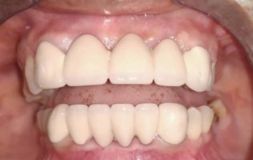

Dental Crowns are a tooth-shaped cap which is placed on the tooth to restore the shape, size, and appearance of the tooth. It also enhances the strength of the tooth. If the major part of the tooth is missing, then the crown is the best solution for it. By placing the crown, a tooth can function normally again.

If you have aesthetic concerns and also wish to have metal crowns inserted then these are the best option available. The inside of the teeth is made up of metal and the outer portion of the crown is made of porcelain, as a result, it has the dual advantage – metal which provides strength and porcelain which matches with the color of the teeth making it look like natural teeth. They look the most like natural teeth.

If you do not want to have metal inserted inside your mouth but want the strength to match metal crowns then ceramic crowns are the best option available. Not only is the strong but blends more naturally with your tooth color making it unnoticed. It does not have any aesthetic concerns and is the best option for the front, back and even for the bridges. The problem of porcelain wearing down and metal being visible is solved by this Dental Crown. They may not be considered as an option for molars because forces applied while biting can wear down your teeth.

There is a misconception that dental crowns do not match with your teeth hence give the impression of an artificial tooth. However, with changes in technology crowns come in various material which looks exactly like your natural teeth. And even metal crowns are a good and viable option because they are used as molars and are never seen.

People believe that one gets crown only if they have fractured tooth, have undergone root canal treatment or have broken or chipped a tooth. But the truth is they are used in cosmetic dentistry as a way to enhance the appearance and to have a whiter and beautiful smile.